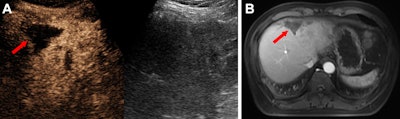

Images depict a 49-year-old male participant with hepatocellular carcinoma following downstaging therapy. (A) Transverse dual contrast-enhanced ultrasound (CEUS) image (left) and B-mode image (right) show the tumor lesion. (B) Image shows an axial contrast-enhanced MRI scan of the tumor lesion. Both CEUS and contrast-enhanced MRI reveal no evidence of residual viable tumor (arrow). Histopathologic analysis further confirmed the absence of residual viable tumor.Images depict a 49-year-old male participant with hepatocellular carcinoma following downstaging therapy. (A) Transverse dual contrast-enhanced ultrasound (CEUS) image (left) and B-mode image (right) show the tumor lesion. (B) Image shows an axial contrast-enhanced MRI scan of the tumor lesion. Both CEUS and contrast-enhanced MRI reveal no evidence of residual viable tumor (arrow). Histopathologic analysis further confirmed the absence of residual viable tumor.RSNA